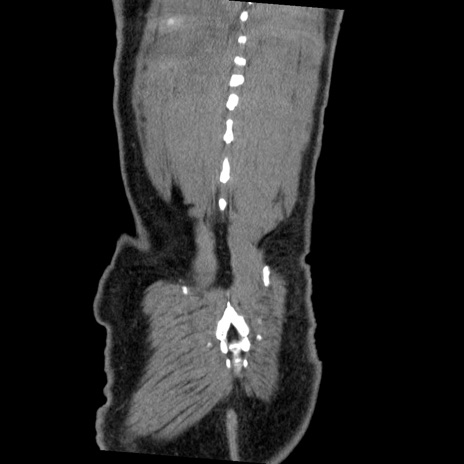

症例22(冠状断像)

【症例】50歳代男性

【主訴】腹痛

【現病歴】AVMからの被殻出血のため回復期リハ病棟入院中。 本日午後3時頃急に下腹部痛が出現した。

【既往歴】AVM、被殻出血、虫垂炎、高血圧

【身体所見】意識晴明、左半身不全麻痺、会話の理解は良好、36.5°C、腹部:膨隆、全体に板状硬、下腹部正中に圧痛点あり、反跳痛-、筋性防御不明、右下腹部にope scar

【データ】WBC 9400、CRP 0.06